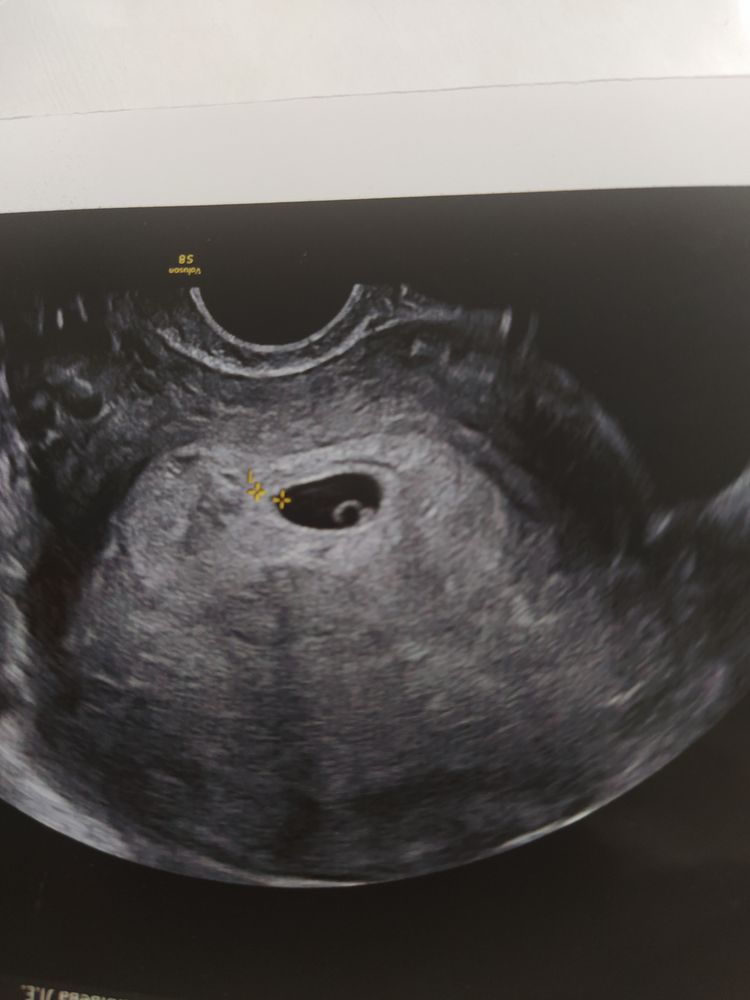

5+4. А кто определять будет? Изображение